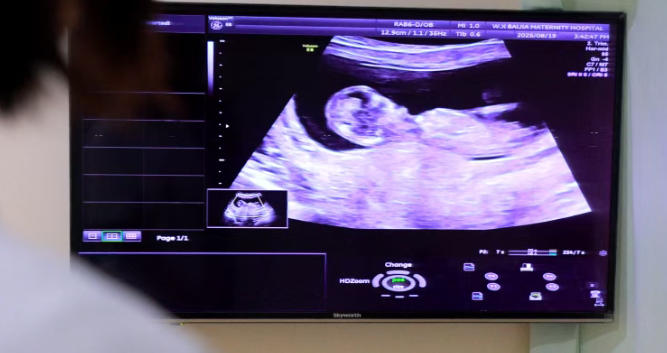

孕中期四维超声九种严重畸形筛查,孕妈妈可点击下图一键预约